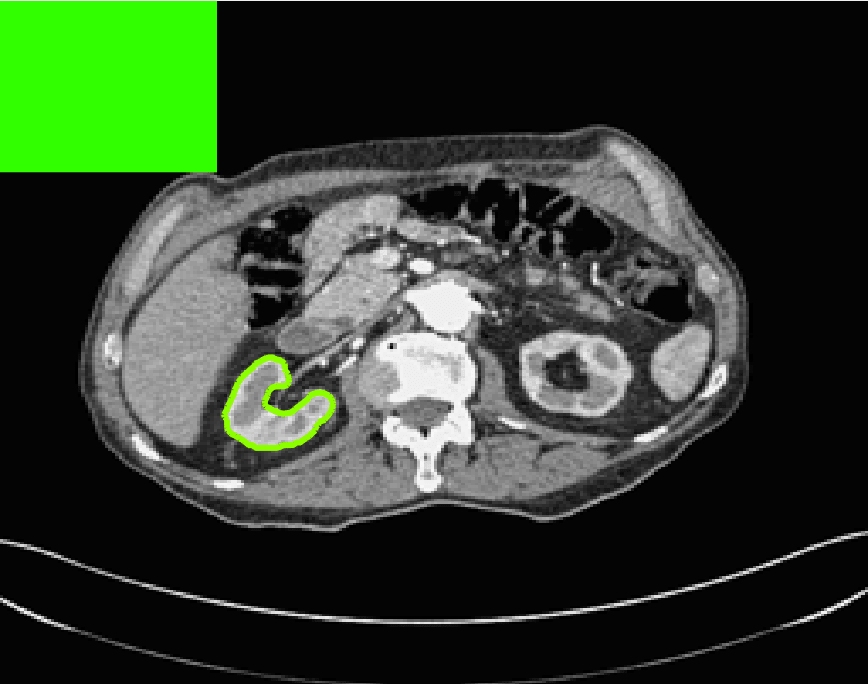

The motivation for this work comes from observing contradictions in using piecewise-constant intensity fitting terms in selective segmentation. Whilst good results are possible with this approach, the exceptional cases lead to severe limitations in practice. This is quite common in medical imaging as demonstrated in Fig. 1, where the target foreground has a low intensity. Given that the corresponding background includes large regions of low intensity, the optimal average intensities for this segmentation problem are and . For cases where , we see that by (1), almost everywhere in the domain . This means that it is very difficult to achieve an adequate result, without an over-reliance on the user input or parameter selection.

| (10) |

where is noise, is the characteristic function of the region , for respectively. The idea of selective segmentation is to incorporate user input to apply constraints that exclude regions classified as foreground, based on their location in the image. We use a distance constraint which penalises the distance from the user input markers. However, a key problem for selective segmentation is that for cases where the optimal intensity values and are similar, the intensity fitting term will become obsolete as the contour evolves. This is illustrated in Fig. 3. The purpose of our approach is to construct a model that is based on assumptions that are consistent with the observed image and any homogeneous target region of interest. A common approach in selective segmentation is to discriminate between objects of a similar intensity Rada:13 ; Geo ; CDSS . However, the fitting terms in previous formulations Klodt:13 ; Rada:13 ; Geo ; CDSS aren’t applicable in many cases as there are contradictions in the formulation in this context. We will address this in detail in the following section.

for and as defined in (33). This is consistent with respect to the intensities of the observed object and the concept of selective segmentation. In Fig. 3 we see the difference between CV and the proposed fitting terms for given user input on a CT image. For the CT image, the CV fitting terms are near 0 within the target region. This is despite there being a distinct homogeneous area with good contrast on the boundary. This illustrates the problem we are aiming to overcome. With the proposed fitting term this phenomenon should be avoided in cases like this. By defining as in (33) there is no contradiction if the foreground and background intensities of the target region are similar.